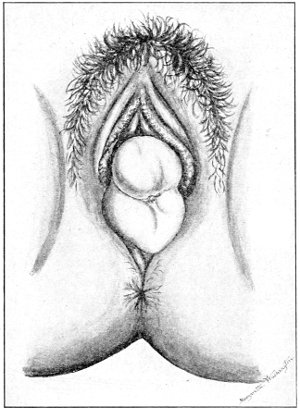

Fig. 16.—Appearance of the external genitals in a woman with gonorrhea: G. m., gonorrheal macula situated at the base of a vaginal caruncle.

Suppuration of the duct may be demonstrated by pressing over the course of the duct, when a drop of pus will escape from the opening. In such cases the orifice of the duct is usually surrounded by a red areola, resembling a flea-bite, which has been called the gonorrheal macula (Fig. 16). This macula persists long after all other traces of inflammation about the vulva and vagina have disappeared, and after all frank suppuration in the duct has subsided. Its presence indicates at least the probability of previous gonorrheal infection.

Suppuration of the vulvo-vaginal gland is accompanied by marked swelling and peripheral edema. The swelling may extend to the anus, and is of characteristic shape (Fig. 17). The pain is always severe. Fluctuation is first apparent on the inner surface of the labium majus. If the condition is not treated, one or more fistulous openings appear below the orifice of the duct, and the pus is discharged. The condition then becomes chronic. The fistulous openings persist. Acute inflammation disappears from the gland, leaving it in a condition of hypertrophic induration. A thin, milky or greenish, purulent fluid may be pressed out of the duct or the fistulous openings. Infection from this discharge may be communicated to man, or may ascend the genital 40 tract, producing inflammation of the endometrium or of the Fallopian tubes.

Fig. 17.—Abscess of right vulvo-vaginal gland.